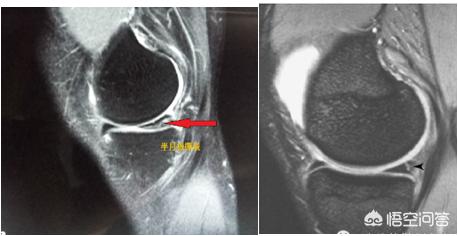

半月板损伤分度,是指膝关节影像学检查MRI显示半月板损伤程度——3度即是三级损伤

半月板撕裂的核磁表现对诊断和对选择治疗方案具有指导意义。

半月板损伤所谓的分级其实是核磁(MRI ) 的分级。MRI 是迄今为止诊断膝关节半月板损伤、交叉韧带断裂等阳性敏感率和准确率最高的影像学检查手段。

正常半月板在MRI中呈均匀的黑色,半月板损伤时可出现异常信号,具体表现为半月板形态、边缘、大小及其内部信号的改变。

半月板损伤的MRI分级

0级:正常;

一级:半月板内有点、球状或椭圆状信号增高影,未达关节面;

二级:半月板内线性的高信号,可延伸至半月板关节囊缘,但不延伸至半节面;

三级:半月板内线状或弥漫性高信号延伸至关节面,即半月板撕裂。

半月板撕裂表现复杂,正确判断半月板撕裂的部位、形态、类型对于临床手术方案的制定非常重要,MRI表现为一、二级为退变信号,比较常见,临床一般没有具体症状,不要为此而纠结。

半月板三度损伤图

核磁出现三级信号者,一般有膝关节疼痛、有时伴有弹响、绞锁,急性期会出现肿胀等症状,建议尽早手术治疗。